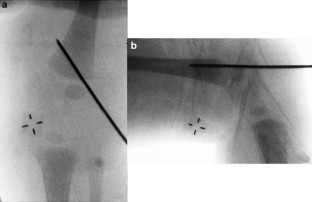

Neonatal physeal fracture of the distal femur is often difficult to diagnose. Timely and accurate diagnosis and appropriate therapy are critical in order to avoid permanent morbidity and dysfunction of the affected limb. We describe an infant in whom closed reduction and pinning were required in order to assure a good outcome.